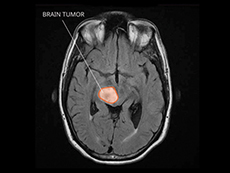

Brain tumor

A liquid biopsy blood test can detect DNA from brain tumors called diffuse midline gliomas, researchers have found. This minimally invasive test could be used to identify and follow molecular changes in children with these highly lethal brain tumors.